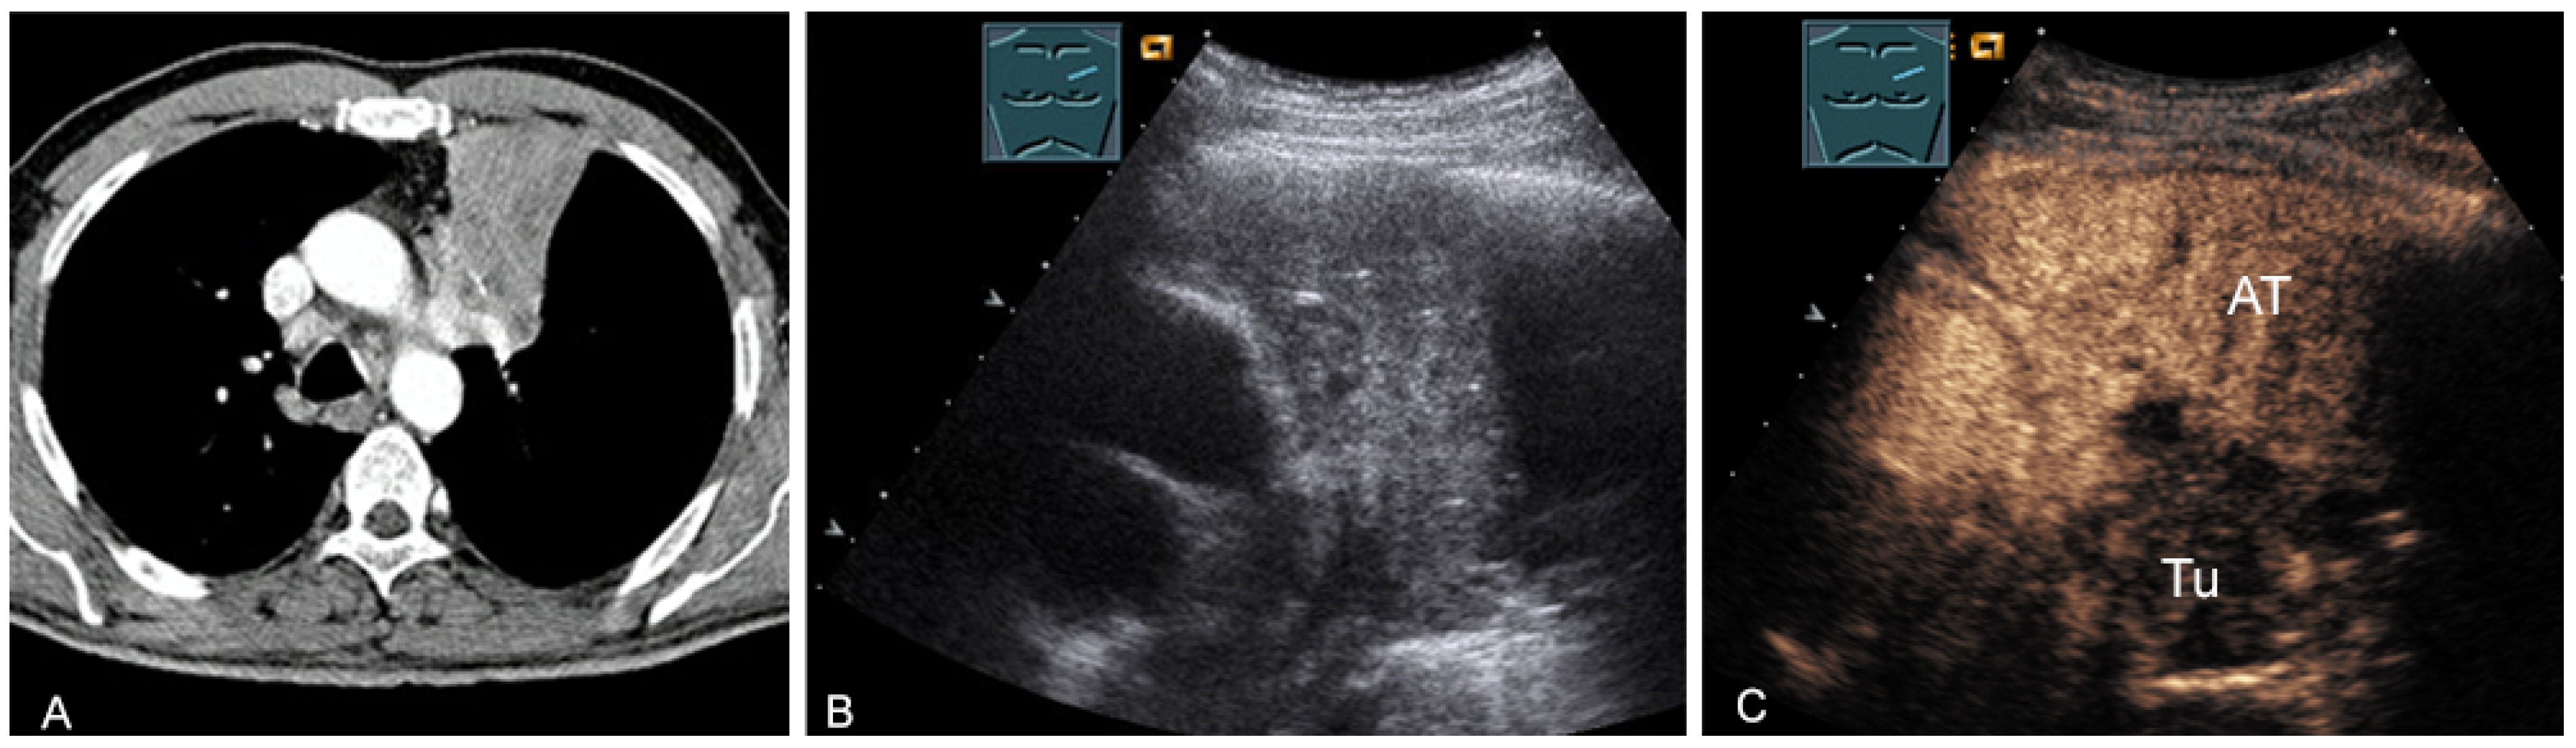

Central bronchial carcinomas can also be sonographically visualized by using the associated atelectasis as an “acoustic window” into the mediastinal processes [38] (Figure 25).

Figure 25.

A patient with mediastinal mass on CT (provided by Prof. Dr. Andreas H. Mahnken, Marburg, Germany) (A), B-mode US (B), and CEUS (C), differentiating bronchial carcinoma (TU; hypoenhancing) from downstream atelectasis (AT, marked enhancement).